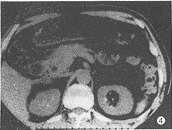

CT表现: 胰头增大2例,胰头及胰钩突增大1例,形态不规则,胰腺组织内小叶结构消失,密度均匀,或有小点状低密度区,与十二指肠紧密粘连,无分界(图4)。胆总管下端管壁一侧不规则增厚、局限性结节各1例(图5)。5例患者均有胆总管扩张(4例有胆道积气),其中胆总管下段逐渐变窄4例,突然中断1例。

图1 胰头腺癌。胰头内局限性低密度区,形态不规则,边缘不清楚,伴有胰、胆管扩张 图2 Vater's壶腹绒毛腺瘤恶变。CT表现为胆总管下端结节,突入十二指肠内侧壁 图3 胆总管癌。胆总管壁均匀增厚,有强化,与周围胰头分界不清,与炎症表现相似,手术见肿瘤沿胆总管壁浸润,达肝门,并有肝门淋巴结转移 图4 胰头炎症。胰头弥漫性肿大,内见散在小点状低密度区,其间胰头实质密度均匀,胰头与十二指肠紧密粘连 图5胆总管下端炎症。CT表现为胆总管下端一侧壁局限性增厚,以上胆道有少许积气,病理切片可见纤维组织增生及慢性炎细胞浸润 图6 胰头癌合并炎症。胰头后部(腔静脉左前侧)见边缘模糊小低密度区,于胰颈部有一炎性假囊肿